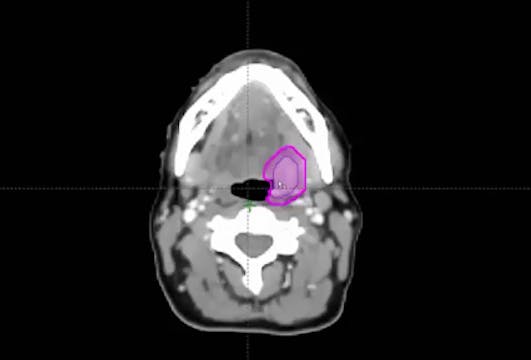

02/26/2024 - Dr. David Sher - Radiation Oncology - Head & Neck

lymph nodes, tonsillectomy, multiple biopsies, HPV positive, NavDx, neck dissection, probability of primary emergence, lingual tonsillectomy, ipsilateral node, right node, toxicity levels, avoid the larynx, base of tongue, skin cancer, balding, postauricular lymph node, biopsy, squamous cell carcinoma, rapid onset, CT scan, PET scan, MRI scan, perineural invasion, carotid, bolus printing, bolus shell, p16 unknown primary, level 1B lymph node, HPV negative,